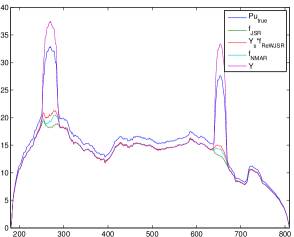

By combining (3.7) with (3.6), the proposed re-weighted JSR model is able to repair the degraded projection so that the repaired data is closer to , where is the Radon domain solution from (3.1) and is the unknown ground-truth CT image. Note that it is hard to obtain the ground truth image for polychromatic energy CT with varying attenuation coefficients with respect to the energy level, we choose the NCAT phantom (Figure 1(a)) as the approximated ground truth CT image . Empirically, the repaired projection data fits the linear inverse problem (1.2) better than the repaired projection data and computed from the NMAR and the unweighted JSR model (3.2) respectively. This is the key to the success of the re-weighted JSR model since the linear model (1.2) is what we commonly assume for CT imaging. Such linear assumption is not correct (though reasonable) for a multi-chromatic imaging system.

To support such claim, we present comparisons of with , , and in Figure 5 using the NCAT phantom. We observe that is a better approximation to the projection of the reference image than the repaired projection data from the JSR and NMAR model (see Figure 5(c),(d)). The NMAR model also generates a better repaired projection than the unweighted JSR model due to its re-weighting strategy. However, the unweighted JSR model is still able to reduce the majority of the metal artifacts in the reconstructed image due to its sparsity based joint regularization. These observations, together with the reconstruction results in Section 4, show that the re-weighted JSR model combines the merits of the NMAR model’s weighting strategy and the sparsity based joint regularization of the unweighted JSR model.

To quantitatively measure the difference between and the repaired projection data from different models and the measured projection data , we calculate the -norms , , and . Since the region of the metal trace has major contribution to these quantities, we also compute the -norms excluding the regions of the metal trace. Results are shown in Table 3. Obviously, the repaired projection data from the re-weighted JSR model is closer to than that from the NMAR and JSR model. However, although is closer to in regions outside of , is overall closer to than due to the inaccurate recovery of the projection data inside the metal trace by the re-weighted JSR model (see Figure 5(c)). This is probably why the re-weighted JSR model still cannot fully remove metal artifacts, though it improves over the unweighted JSR and the NMAR model.